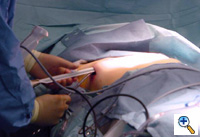

Once the tunnel reaches the sternum, the endoscopic tunneling device is utilized to visualize the clamp entering the interspace of maximal pectus depth and passing retrosternal (Figure 7). At the level of the sternum, these tunnels go retrosternal and communicate with each other. Ideally, even after entering the interspace, the tunnel stays extrapleural. The endoscopic view of the tunnel allows visualization of the safe passage of the clamp under the sternum and anterior to the pericardium. The mediastinum and pericardium can be seen pulsating posterior to the clamp. Two monitoring screens are utilized in order to allow excellent visualization by both the surgeon and assistant (Figure 8). Eventually, the larger curved clamp is easily passed under the sternum (Figure 9). This clamp is thus passed through one midaxillary skin incision and out the other midaxillary skin incision.

The clamp is then opened and used to grasp an umbilical tape and pull the tape through the tunnel (Figure 10). This umbilical tape is tied to two more umbilical tapes so that one tape can be used to pull a flat mediastinal tube through the tunnel and the second umbilical tape can act as a back-up. One umbilical tape is tied to a flat mediastinal tube. Then, this flat mediastinal tube is lubricated (Figure 11) and pulled through the tunnel and used to gently dilate the tunnel. The tunnel pathway is then endoscopically inspected to confirm hemostasis and satisfactory position of the flat mediastinal tube (Figure 12 ).

The mediastinal tube is again irrigated and lubricated internally and externally with antibiotic solution. The previously shaped steel bar is then passed through the retrosternal space within the flat silastic mediastinal drain, thereby protecting surrounding mediastinal structures. The flat mediastinal tube provides some protection as the bar passes retrosternal through the tunnel. Thus, the curved steel bar is passed through one tunnel, under the sternum, and out the other tunnel. The steel bar is inserted with the convexity facing posteriorly (Figure 13). Once the bar is within the tunnel and in a retrosternal position, the flat mediastinal tube and back-up umbilical tape are removed. The bar edges are flared inward bilaterally. The bar is then rotated so that the convexity faces anteriorly, thereby correcting the deformity. Very slight over-correction by design is evident.